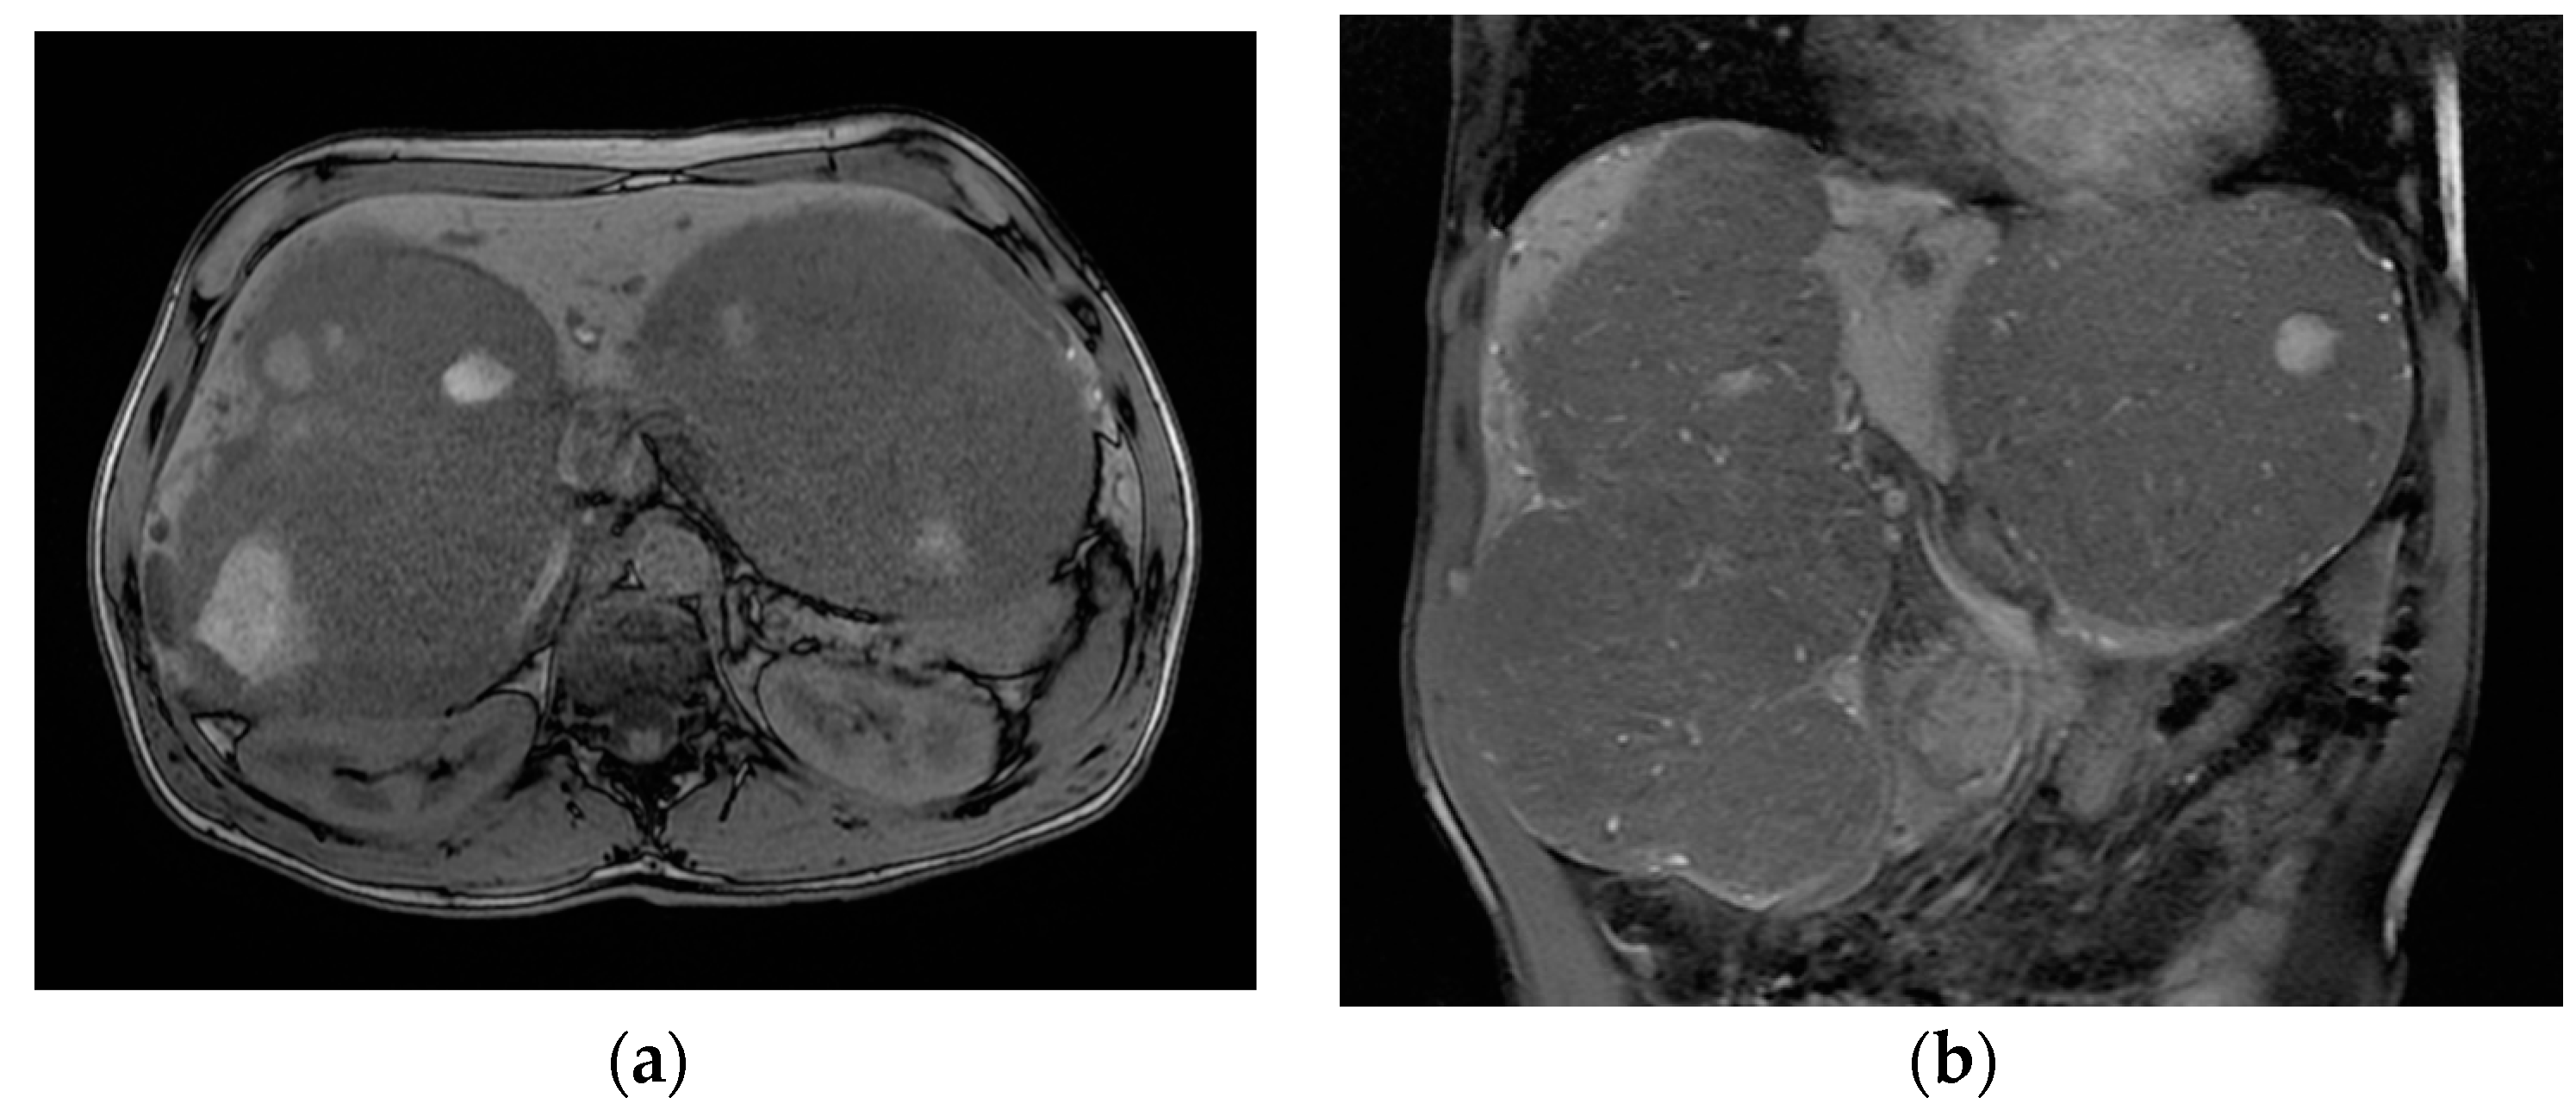

The patient was referred to our tertiary hepato-bilio-pancreatic surgery center to reassess GLM resectability. At this point, the patient was handicapped due to the giant metastases impeding walking and breathing; the ECOG performance status was 4, and the Charlson comorbidity index was 6. At imaging, aside from several small metastases in the central part of the liver (liver segments 4, 5, and 8), there were two large groups of confluence metastases: One was 17/10 cm in size, completely occupying segments 6 and 7, partly occupying segments 5 and 8, and invading the right hepatic vein. The other was 14/11 cm in size, occupying the entirety of segment 2, partly occupying segments 3 and 4 superior, and invading the left hepatic vein (Figure 4). Total liver volume was 5092 cm3; left hemiliver volume was 1876 cm3, while right hemiliver volume was 3217 cm3.

Figure 4.

MRI showing the two groups of large liver metastases: (a) one group located in segments 6 and 7 and partly in segments 5 and 8, invading the right hepatic vein, while (b) the other occupied the entirety of segment 2 and partly occupied segments 3 and 4 superior, invading the left hepatic vein.